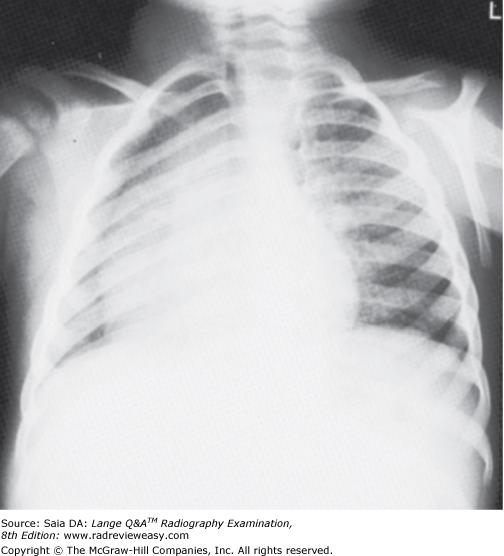

Which of the following statements is (are) true regarding the radiograph shown in Figure 6–16?

- The part is rotated.

- The patient is not shielded correctly.

- There is excessive receptor exposure.

A 1 only

B 2 only

C 1 and 2 only

D 1, 2, and 3

-The patient is well positioned; the spinous processes and sternum are seen clearly without superimposition. Adequate penetration and long-scale contrast are present without excessive receptor exposure. The patient had been shielded properly for the PA projection, but the shield was not moved to the correct location prior to the lateral exposure.